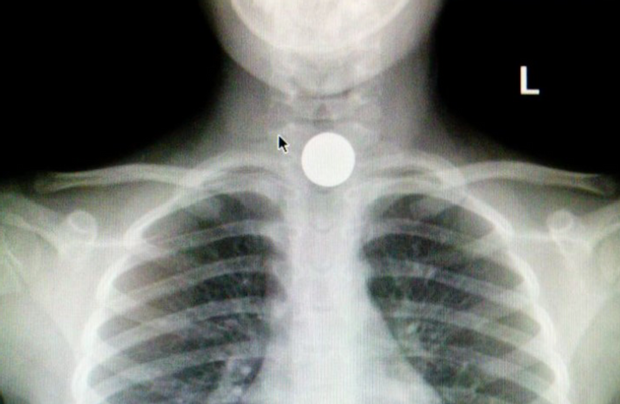

Однак, дива, як на відео не сталося, а дівчина проковтнула монету, яка ще й застрягла в стравоході. Через це дівчинка ледь не задихнулася, але врятувати доньку встигли батьки. Тому вони швидко зреагували й відвезли дитину до лікарні.

Лікарі зробили рентгенівський знімок. Медики зазначили, що здоров'ю дівчинки нічого не загрожує, а блогер після розголосу видалив небезпечне відео.

Рентген дівчинки, на якому видно монетку (скрін з відео)